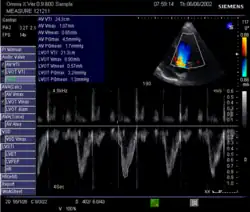

Doppler ultrasound

Doppler signal in the left ventricular outflow tract: Velocity Time Integral (VTI)

This method uses ultrasound and the Doppler effect to measure cardiac output. The blood velocity through the heart causes a Doppler shift in the frequency of the returning ultrasound waves. This shift can then be used to calculate flow velocity and volume, and effectively cardiac output, using the following equations:

where:

• CSA is the valve orifice cross sectional area,

• r is the valve radius, and,

• VTI is the velocity time integral of the trace of the Doppler flow profile.

Being non-invasive, accurate and inexpensive, Doppler ultrasound is a routine part of clinical ultrasound; it has high levels of reliability and reproducibility, and has been in clinical use since the 1960s.